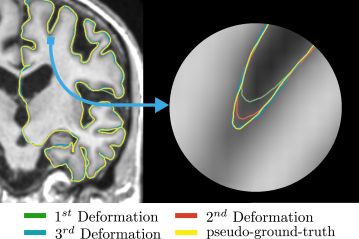

As shown in Figure 2, CorticalFlow consists of a chain of three deformations. Note that more deformation modules could be used, but we focus on three modules to have a fair comparison with existing techniques. The first deformation module receives as input a volumetric image and outputs a flow vector field with the same dimensions using UNet-3D [63]. This discrete flow vector field is integrated by the DMD module to compute smooth deformations as explained in Section 3.1. The subsequent UNet-3D receives as input the image and the flow vector fields predicted by the previous deformation modules. The set of resulting mappings are composed to produce the final mesh.

As explained in subsection 3 of our paper, CorticalFlow leverages a chain of 3 deformation blocks to provide a coarse-to-fine approximation of the targeted surface. We evaluate CorticalFlow predictions after each deformation block in our cortical surface reconstruction benchmark to empirically validate this modeling decision. As shown in Table 2, every deformation block added allows a better approximation of the ground-truth surfaces. More specifically, on average across all surfaces, adding a second deformation block reduces the Chamfer distance metric by 36.73%, while adding a third deformation block reduces the same metric by a further 5.06%. Importantly, this error reduction is more evident in the sulci region of the cortical surfaces, as shown by the example depicted in Figure 7.

As shown in Figure 2 of our paper, CorticalFlow consists of a chain of three deformation blocks. Each of these deformations is implemented by some UNet flow vector field predictor and the Diffeomorphic Mesh Deformation (DMD) module described in subsection 3.1 of our paper. More specifically, the first deformation block uses our architecture while the remaining ones use our architecture. Both architectures are described in details in Figure 8. As explained in subsection 3.2, the reason for this architectural change is to promote the learning of a coarse-to-fine sequence of deformation blocks.